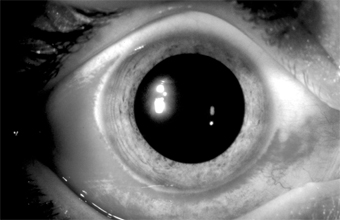

Herpes simplex virus (HSV) conjunctivitis, usually a disease of young children, is an uncommon entity characterized by unilateral injection, irritation, mucoid discharge, pain, and mild photophobia. It occurs during primary infection with HSV or during recurrent episodes of ocular herpes (Figure 5-7). It is often associated with herpes simplex keratitis, in which the cornea shows discrete epithelial lesions that usually coalesce to form single or multiple branching epithelial (dendritic) ulcers. The conjunctivitis is follicular or, less often, pseudomembranous. (Patients receiving topical antivirals may develop follicular conjunctivitis that can be differentiated because the herpetic follicular conjunctivitis has an acute onset.) Herpetic vesicles may sometimes appear on the eyelids and lid margins, associated with severe edema of the eyelids. Typically, there is a small tender preauricular node.

Figure 5-7

Figure 5-7: Primary ocular herpes. (Courtesy of HB Ostler.)

No bacteria are found in scrapings or recovered in cultures. If the conjunctivitis is follicular, the predominant inflammatory reaction is mononuclear, but if it is pseudomembranous the predominant reaction is polymorphonuclear owing to the chemotaxis of necrosis. Intranuclear inclusions (because of the margination of the chromatin) can be seen in conjunctival and corneal cells if Bouin fixation and the Papanicolaou stain are used but not in Giemsa-stained smears. The finding of multinucleated giant epithelial cells has diagnostic value.

The virus can be readily isolated by gently rubbing a dry cotton-tipped applicator over the conjunctiva and transferring the infected cells to a susceptible tissue culture.

HSV conjunctivitis may persist for 2-3 weeks, and if it is pseudomembranous it may leave fine linear or flat scars. Complications consist of corneal involvement (including dendrites) and vesicles on the skin. Although type 1 herpesvirus causes the overwhelming majority of ocular cases, type 2 is the usual cause in newborns and a rare cause in adults. In the newborn, there may be generalized disease with encephalitis, chorioretinitis, hepatitis, etc. Any HSV infection in the newborn must be treated with systemic antiviral therapy (acyclovir) and monitored in a hospital setting.

If the conjunctivitis occurs in a child over 1 year of age or in an adult, it is usually self-limited and may not require therapy. Topical or systemic antivirals should be given, however, to prevent corneal involvement. For corneal ulcers, corneal debridement may be performed by gently wiping the ulcer with a dry cotton swab, applying antiviral drops, and patching the eye for 24 hours. Topical antivirals alone should be applied for 7-10 days: trifluridine every 2 hours while awake, or vidarabine ointment five times a day, or idoxuridine 0.1%, 1 drop every hour while awake and 1 drop every 2 hours during the night. Herpetic keratitis may also be treated with 3% acyclovir ointment (not available in the USA) five times daily for 10 days or with oral acyclovir, 400 mg five times a day for 7 days. The use of steroids is contraindicated, since they may aggravate herpes simplex infections and convert the disease from a short, self-limited process to a severe, greatly prolonged one.